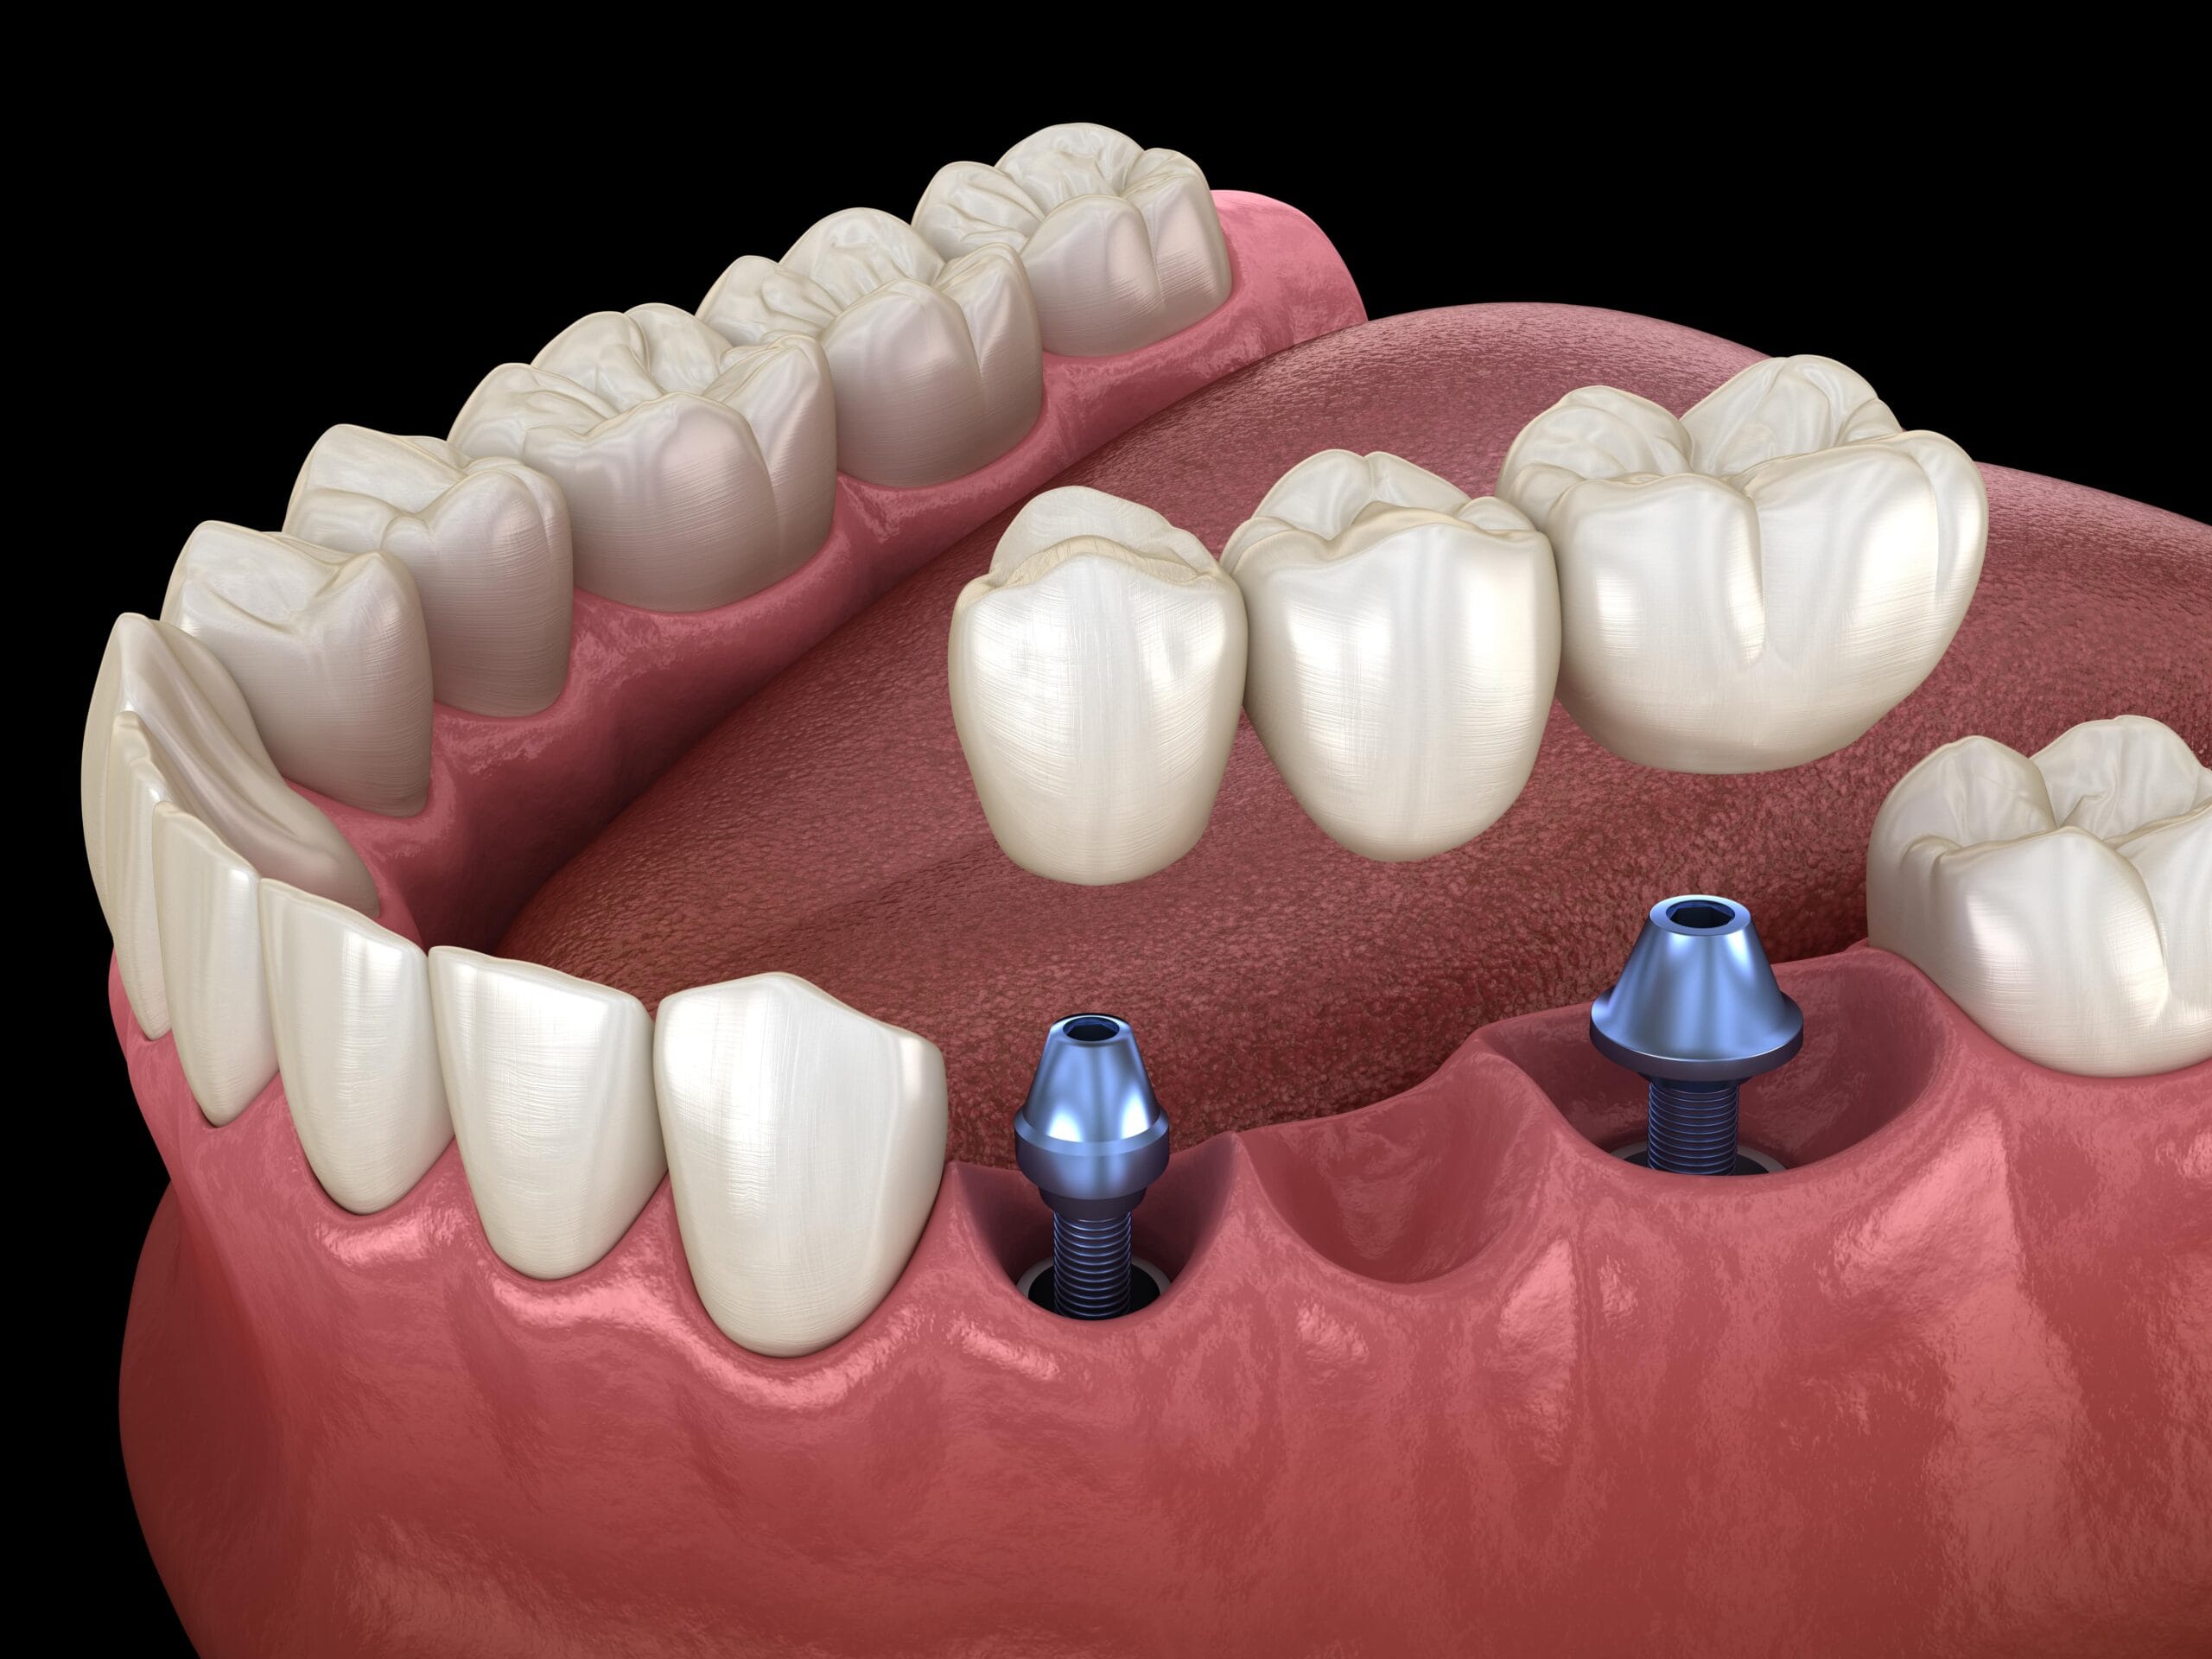

Dental implants and prosthodontic treatments focus on replacing missing teeth and restoring oral function, comfort and aesthetics. These

treatments help improve chewing ability, speech and overall confidence.

Crowns and bridges are recommended to restore damaged or missing teeth,

improve strength and protect remaining tooth structure while maintaining

natural appearance.